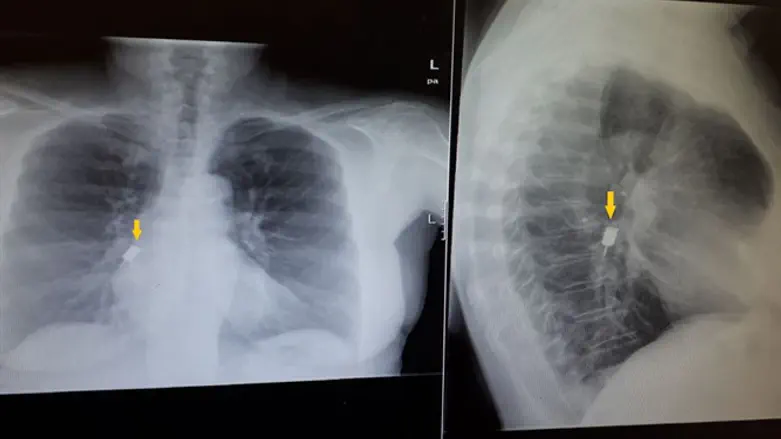

צוות חדר המיון הרגיע את המטופלת המבוהלת וערך בדיקות וצילום רנטגן חזה, בו זוהה בבירור, גוף זר בעל חוד ארוך, נעוץ עמוק כלפי מטה, ממוקם בהתפצלות סימפון הריאה הימנית.

"בפעולה מורכבת, תחת הרדמה מלאה ובאמצעות ברונכוסקופ פיבראופטי, מכשור עדין במיוחד, חולץ העצם הזר שצדו החד היה נעוץ בחוזקה בעומק הריאה הימנית וכל זאת בלא שנפתחו התפרים ובלי שנגרם כל נזק נוסף למיתרי הקול או במעברי האוויר. צוות גדול ממחלקת אף אוזן גרון ניצב בהיכון לצדי, לאורכו של כל ההליך עם הציוד הקשיח שברשותם, למקרה צורך בנקיטת צעדים חריפים יותר לחילוץ העצם הזר, שהיה מצוי עמוק מאוד בתוך הריאה במצב מסכן חיים", אמרה ד"ר עמיטל